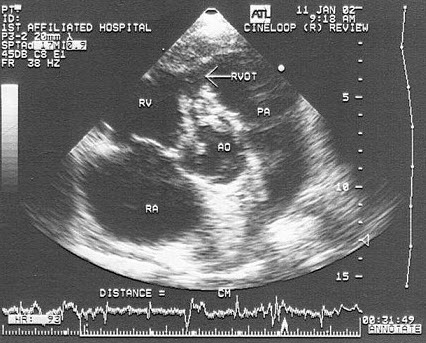

9、单项选择题

该病例最可能的诊断()

A.右室双出口并室间隔缺损

B.主动脉骑跨

C.室间隔缺损

D.大动脉异位

E.左室双出口